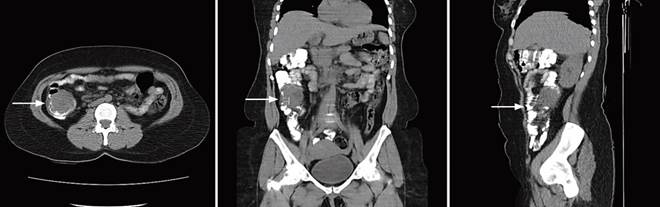

Therefore, the patient attended the emergency department. During the interrogation, she reported a condition of intestinal intussusception ten months ago of unknown cause, which self-resolved and required hospitalization for three days. Considering this and the abdominal pain, a contrast-enhanced abdomen CT was requested, describing a lipomatous-type lesion at the ascending colon level (Figure 2).